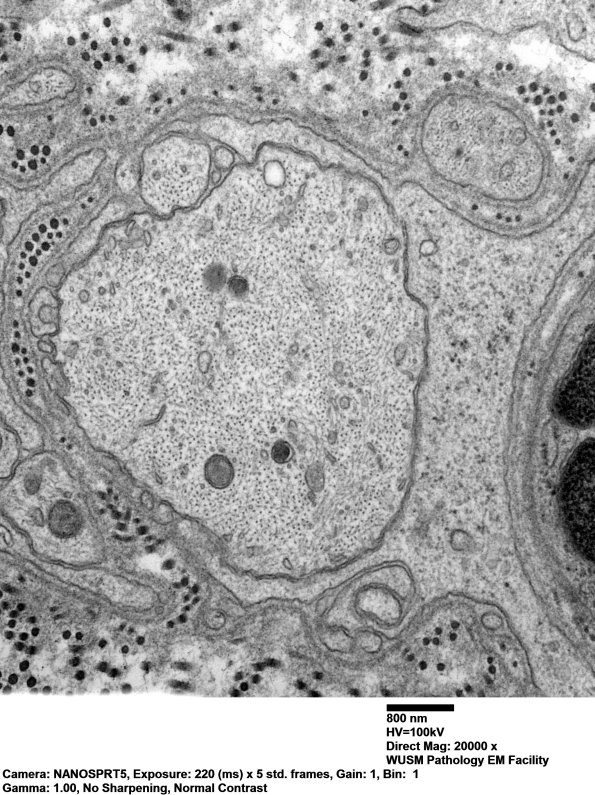

A large demyelinated axon shows a prominent cytoskeleton. Electron microscopy shows no evidence of macrophage-mediated demyelination (i.e., no definitive pathognomonic correlate of Guillain-Barre syndrome) (electron micrographs)